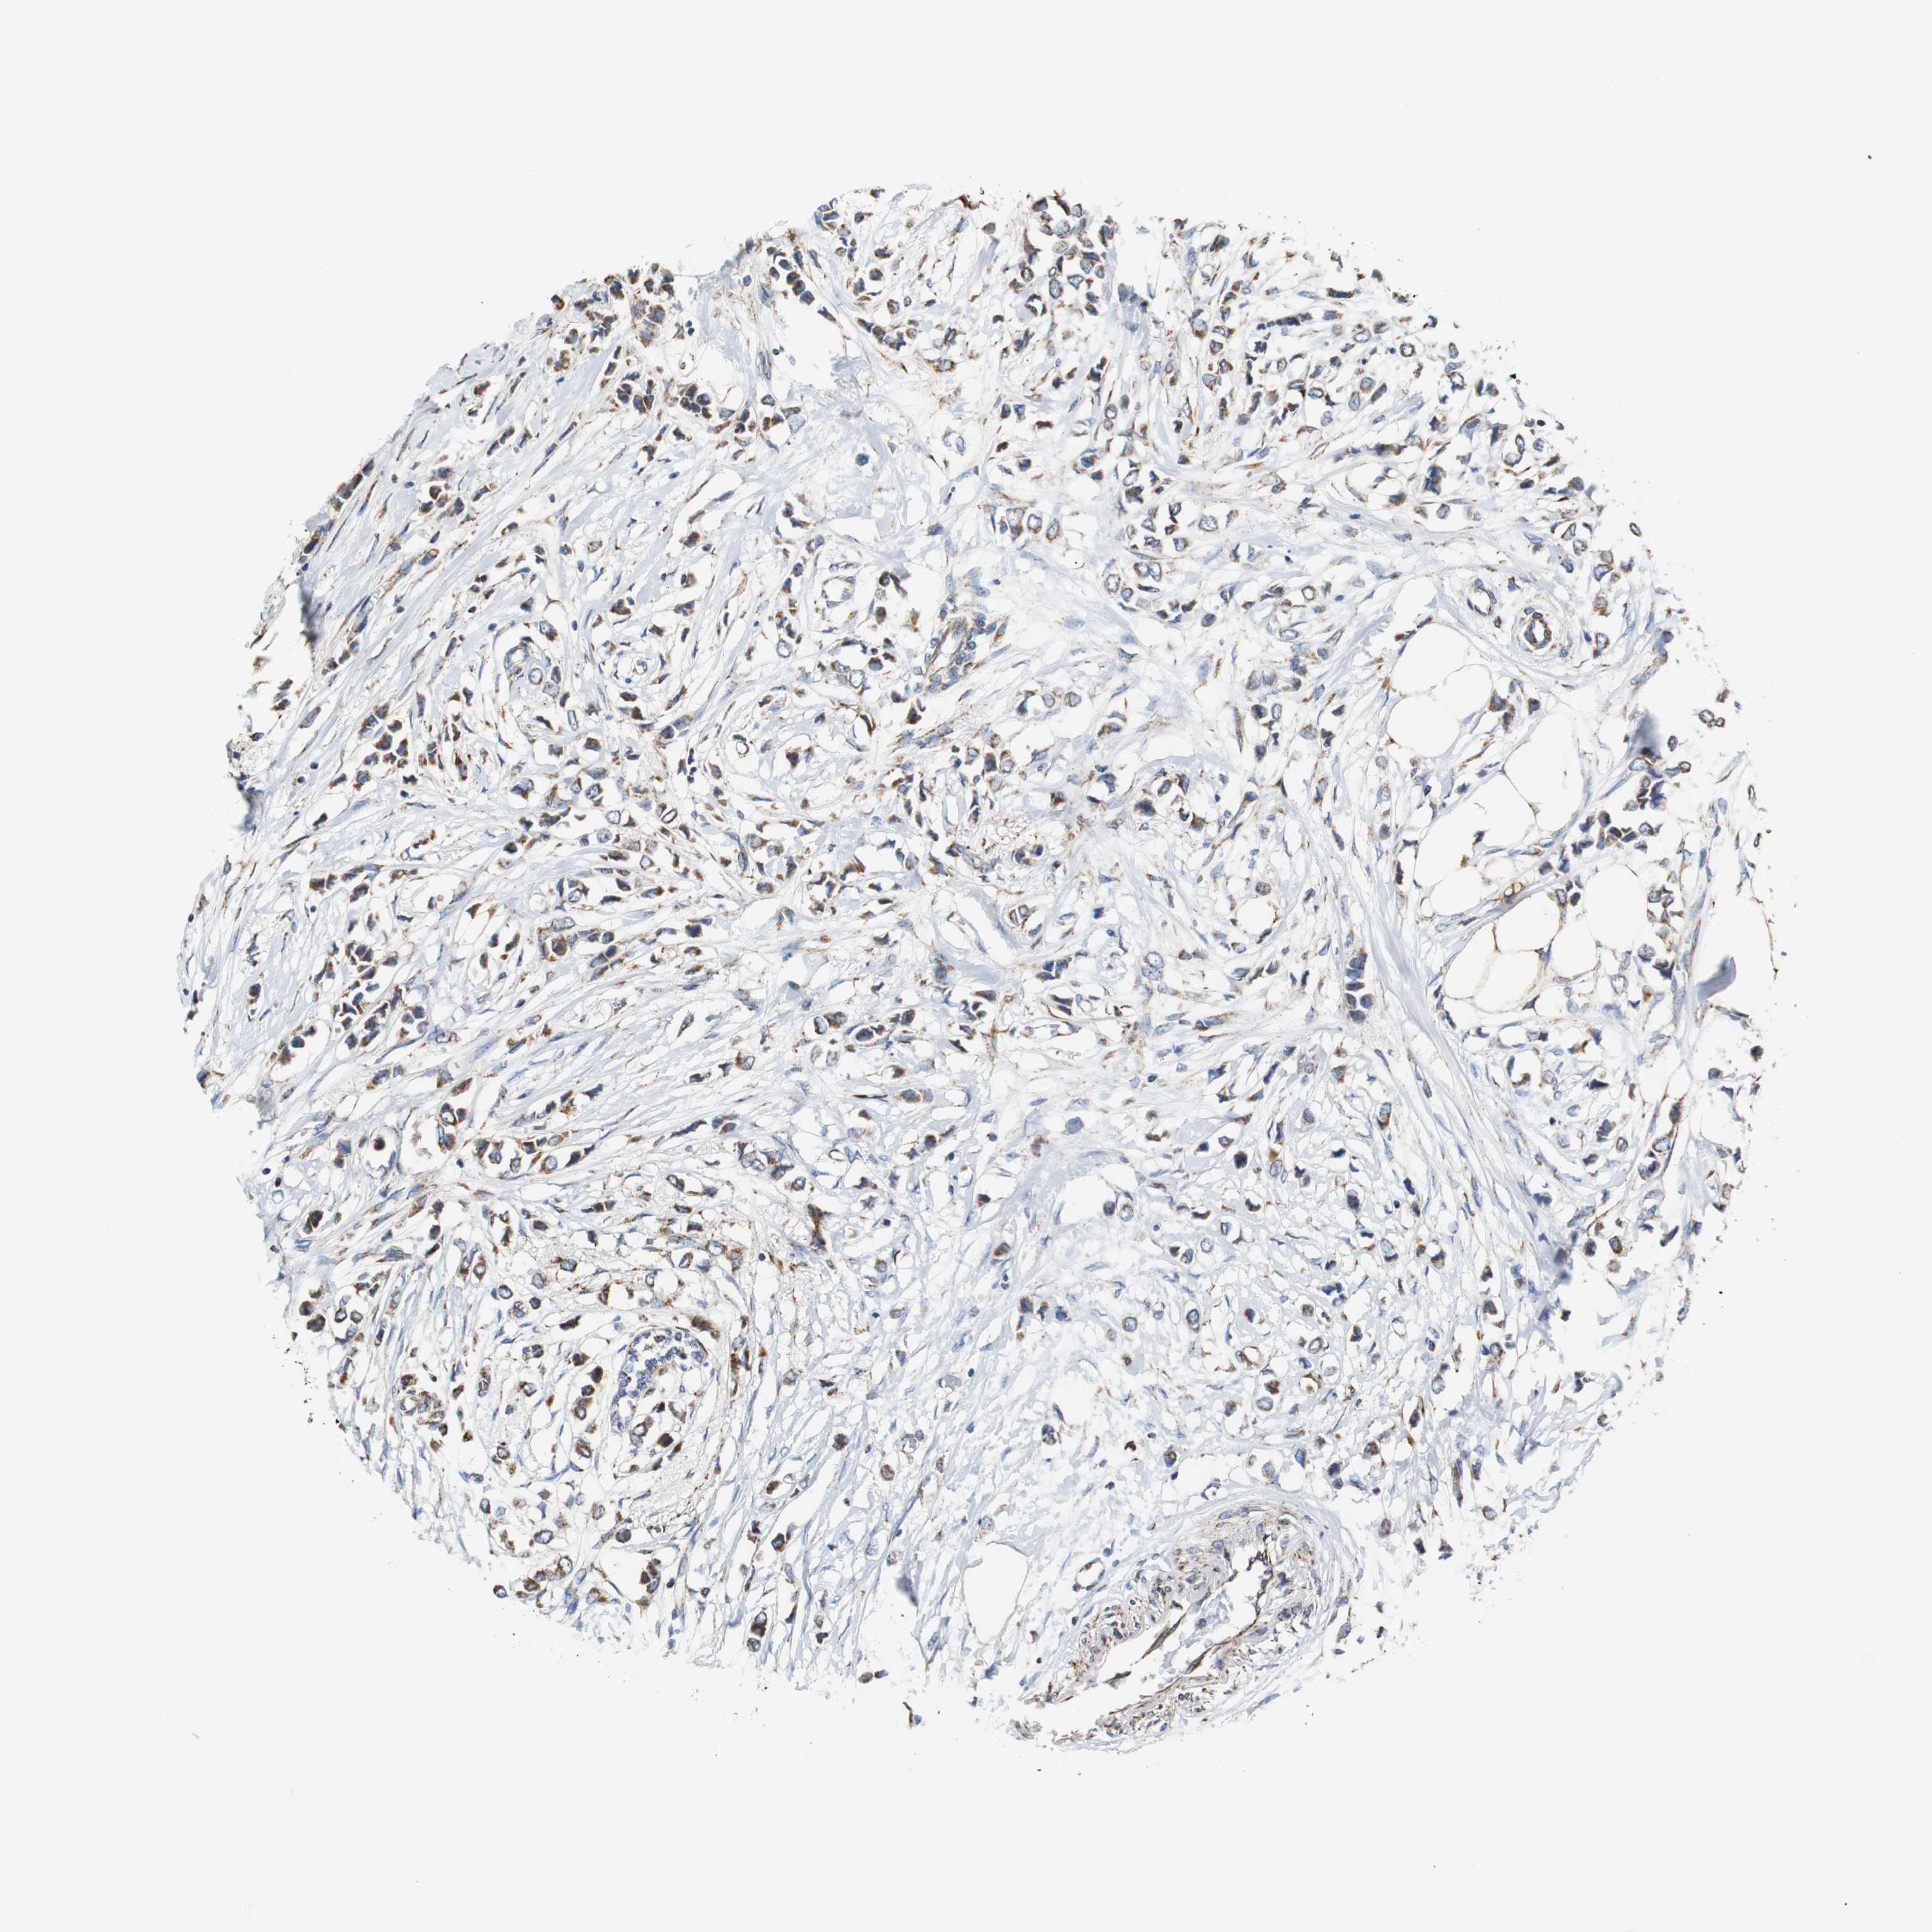

CANCER BREAST CANCER Show tissue menu

BRCA TCGA BRCA VALIDATION PROTEIN EXPRESSION